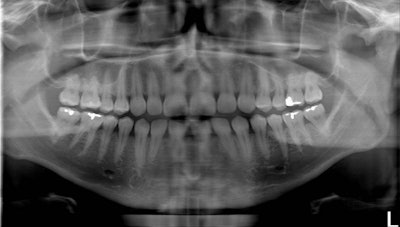

Standard panoramic image from a PC-1000 system using a CdTe sensor from Ajat, self-corrected with tomosynthesis software. Images courtesy of Dr. Robert Langlais.

Although the front teeth are distorted, the back teeth are no longer crossed. By manually positioning the patient in the system, the contacts are now open.

The tomosynthesis software then autocorrected the image to bring the front teeth into focus.